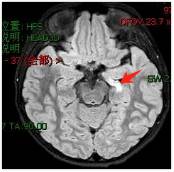

海马硬化:颞叶癫痫的常见病因,手术切除可能根治。

图中箭头为1.5岁女孩左侧海马硬化,手术切除后无发作